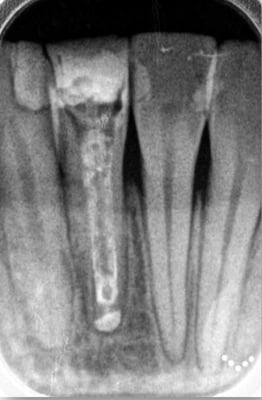

歯根端切除術 Apicopectomy

下顎前歯 root endo sealing

術後4年。